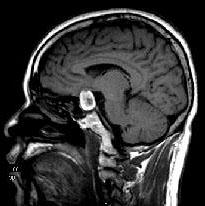

问题 男性,55岁,头痛1年余,2个小时前突然出现剧烈头痛,MRI检查如图所示,最可能的诊断为()

选项 A.垂体瘤 B.脑膜瘤 C.颅咽管瘤 D.垂体瘤并卒中 E.动脉瘤

答案 D